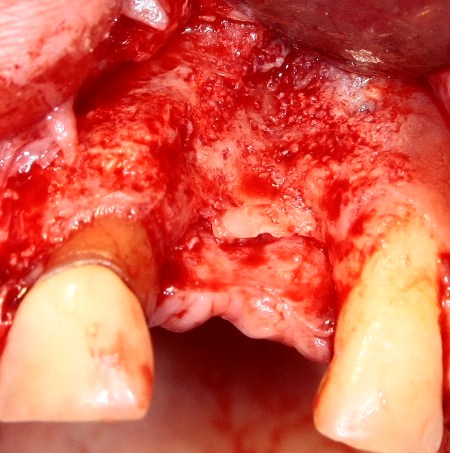

Прежде, чем приступить к аугментации (пластике) лунок зубов, мы подготовили лунки для имплантатов. В таких клинических случаях нет необходимости в использовании шаблона. Вместо этого, мы применяем общепринятые правила позиционирования и соблюдаем рекомендации производителя по хирургическому протоколу:

В процессе ирригации лунки промываются, что позволило нам еще раз подтвердить ранее сделанные выводы. С помощью аналогов имплантатов, входящих в хирургический набор Xive, мы проверили возможность стабилизации имплантатов в будущих лунках. Исходя из правил подбора и позиционирования имплантатов (я очень рекомендую почитать об этом здесь>>) мы остановились на Xive S диаметром 3,4 мм и длиной 13 мм.

Подготовка двух лунок для имплантатов занимает около 10 минут.